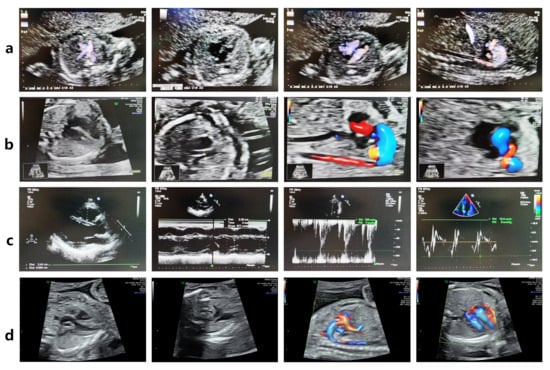

Figure 2. The FLNC variant leads to fetal Tetralogy of Fallot (TOF). (a) Fetal echocardiography at 22 weeks of gestation revealed TOF (pulmonary valve stenosis, ventricular septal defect, overriding aorta, and right ventricular hypertrophy) in the FLNC variant-carrying fetus IV-3. (b) Fetal echocardiography at 20 + 3 weeks of gestation revealed TOF in the proband IV-4. (c) The woman III-7 carries the FLNC variant but has a normal echocardiogram. (d) The fetus IV-5, who does not carry the FLNC variant, exhibited a normal echocardiogram at 23 weeks of gestation.

In 2017, a 35-year-old woman with a history of infertility (III-7, Figure 1a) conceived through in vitro fertilization. Prenatal echocardiography identified TOF in the fetus (IV-3) at 22 weeks of gestation. The diagnosis included pulmonary valve stenosis, ventricular septal defect, shifting of the aorta, and right ventricular hypertrophy, as illustrated in Figure 2a. The karyotype and chromosomal microarray analysis (CMA) results were normal. After genetic counseling and informed consent, the pregnancy was electively terminated.

In 2019, a subsequent embryo transfer resulted in another pregnancy. Fetal echocardiography at 20 weeks and 3 days again revealed TOF in the proband (IV-4) (Figure 2b). The karyotype and CMA results were normal.

Third Generation (Mother and Siblings): III-7 (mother) carried the variant but remains asymptomatic (Figure 2c). Among II-8’s children, III-9 carried the variant and was diagnosed with an atrial septal defect (ASD), consistent with previous reports [11], whereas III-8 did not carry the variant and exhibited no cardiac abnormalities.

In 2022, the family opted for PGT. An embryo confirmed to be negative for the FLNC variant was selected for transfer. Prenatal WES and Sanger sequencing at 18 weeks’ gestation verified the absence of the variant, and fetal echocardiography at 23 weeks demonstrated normal cardiac anatomy (Figure 2d). Postnatal echocardiography and electrocardiography were likewise normal.